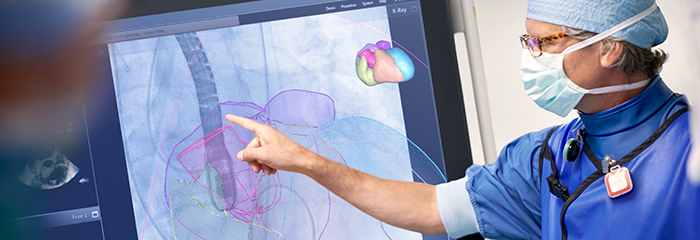

Image Guided Therapy System—Azurion

Azurion provides the ability to treat one more patient per day, reducing procedure time by 17%* with optimized workflow options in interventional therapy and clinical software. *Reducing procedure time by 17%, with the ability to treat 1 more patient per day with optimized workflow options in image guided therapy and clinical software (Azurion - Philips Azurion Simulation Study 2016 - 12NC 452299123041 - FEB 2017). Results are specific to the institution where they were obtained and may not reflect the results achievable at other institutions.